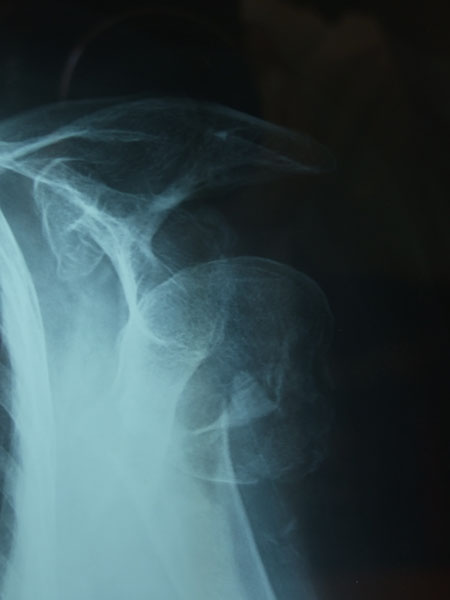

Fractura de húmero, intensa desviación de fragmentos